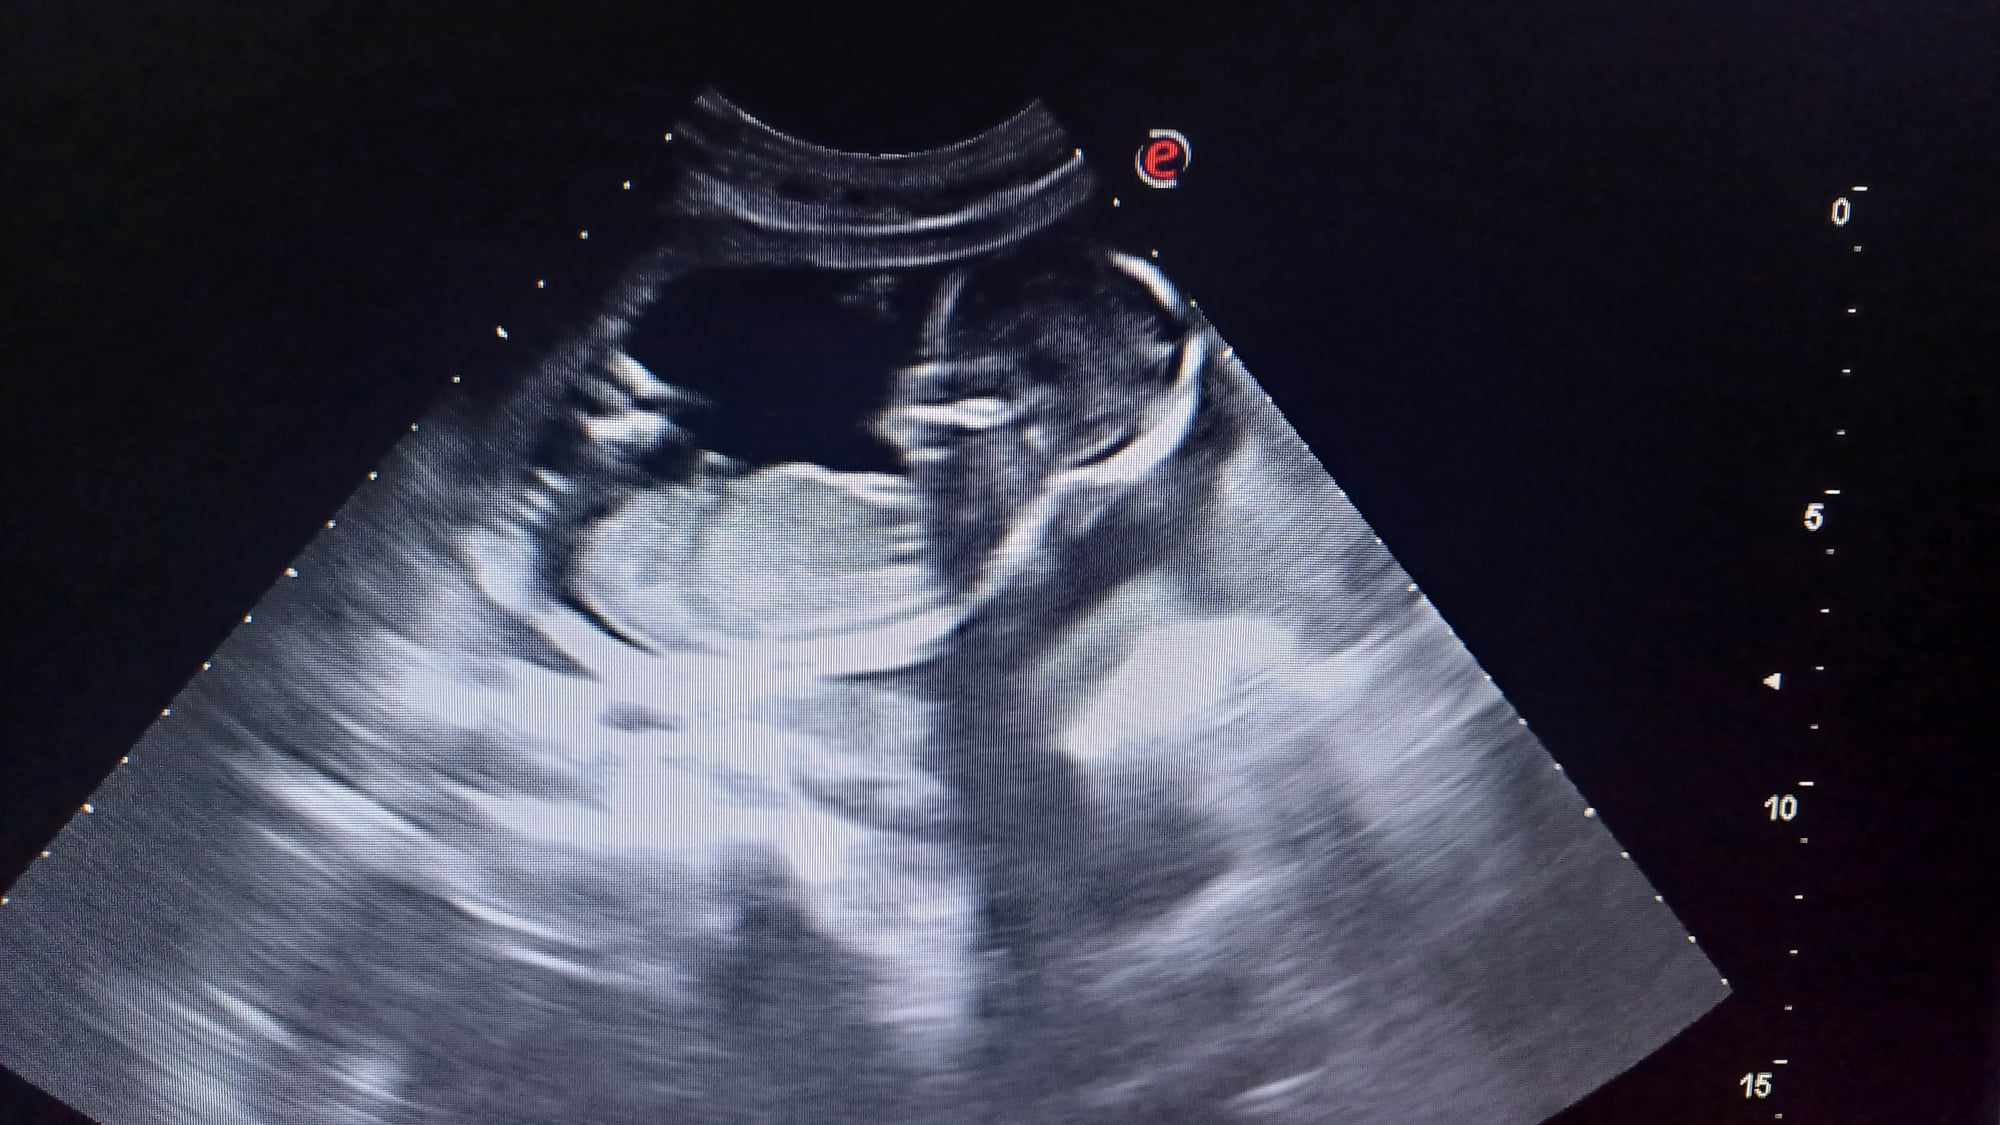

Pozrite si fotky z nášho moderného pracovného prostredia

Naša gynekologická ambulancia je vybavená modernou technikou a poskytuje pacientkom príjemné a komfortné prostredie pre všetky druhy vyšetrení a konzultácií.